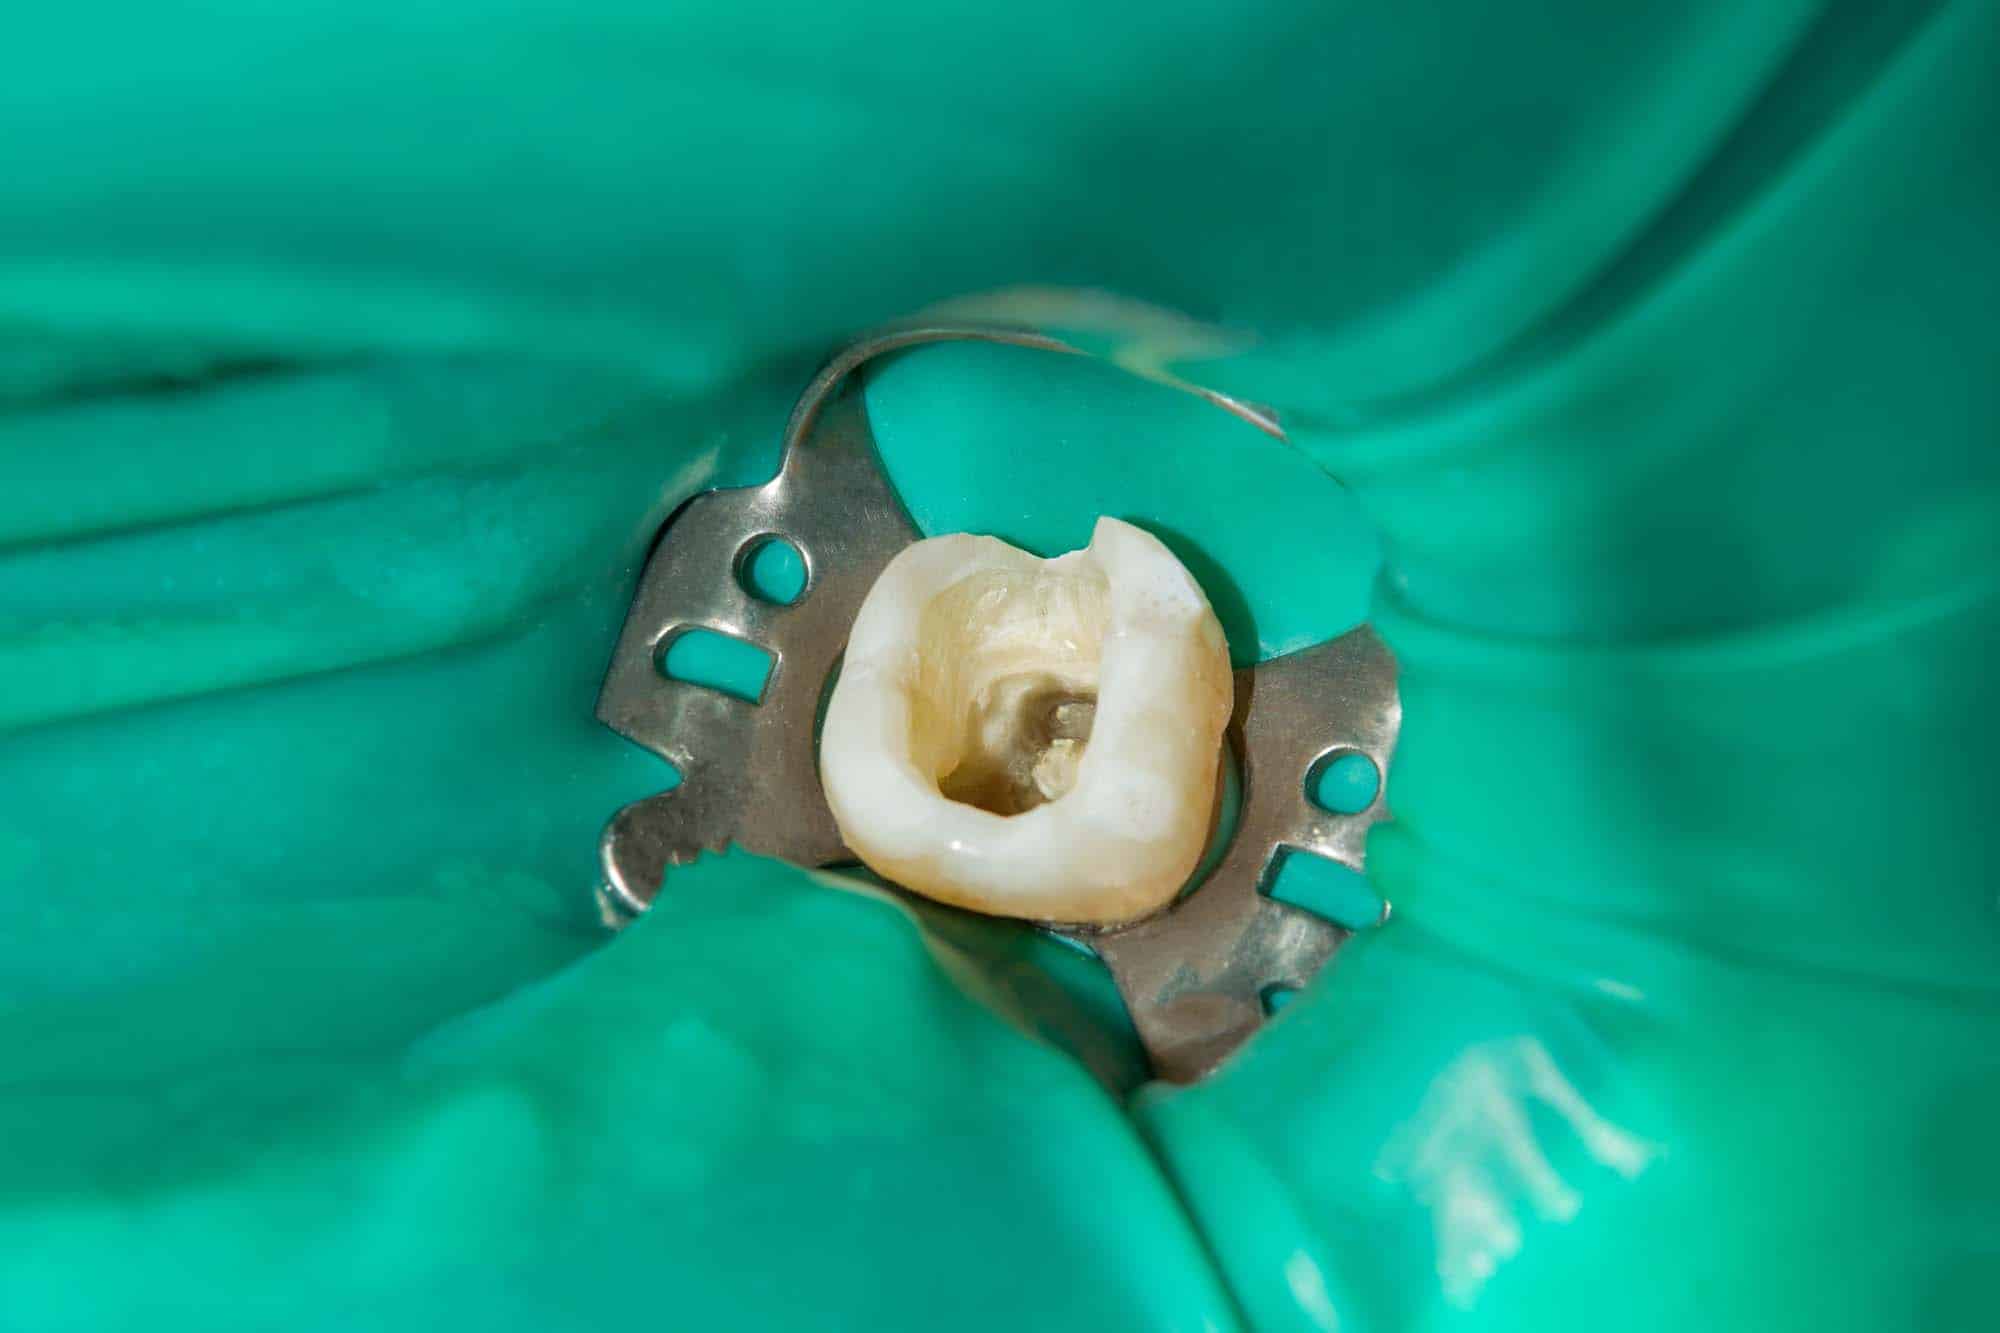

Root Canal Specialist Wimbledon . A passionate dentist & member of the british endodontic society, has a special interest in root. To book an appointment with dr aaron, call 020 8946 2255. Effective treatment for infected teeth. Decay, caries or trauma can cause irreversible damage to. Dr aaron yusuf is one of the most experienced dentists (endodontist) for root canal treatment in wimbledon. Root canal treatment has a high success rate and its purpose is to eliminate and prevent disease reoccurring inside the tooth. 91a the broadway, wimbledon, london, sw19 1qe. Compare all the dentists and contact the root canals clinic in wimbledon that's right for you. All dentists are trained to carry out simple. Dr aaron yusuf is a partner at ridgway dental. Who performs root canal treatment? Call today on 020 8542 2171 to book consultation. Our root canal dentist can help to remove infected pulp from tooth. Root canal treatment in wimbledon.

Root Canal Specialist Wimbledon Dr aaron yusuf is one of the most experienced dentists (endodontist) for root canal treatment in wimbledon. Decay, caries or trauma can cause irreversible damage to. Our root canal dentist can help to remove infected pulp from tooth. Effective treatment for infected teeth. Call today on 020 8542 2171 to book consultation. Who performs root canal treatment? Root canal treatment has a high success rate and its purpose is to eliminate and prevent disease reoccurring inside the tooth. Compare all the dentists and contact the root canals clinic in wimbledon that's right for you. 91a the broadway, wimbledon, london, sw19 1qe. To book an appointment with dr aaron, call 020 8946 2255. A passionate dentist & member of the british endodontic society, has a special interest in root. All dentists are trained to carry out simple. Dr aaron yusuf is one of the most experienced dentists (endodontist) for root canal treatment in wimbledon. Dr aaron yusuf is a partner at ridgway dental. Root canal treatment in wimbledon.

Root Canal Treatment Wimbledon Book Consultation Infinitidental Clinic Root Canal Specialist Wimbledon A passionate dentist & member of the british endodontic society, has a special interest in root. All dentists are trained to carry out simple. Call today on 020 8542 2171 to book consultation. Our root canal dentist can help to remove infected pulp from tooth. Compare all the dentists and contact the root canals clinic in wimbledon that's right for. Root Canal Specialist Wimbledon.